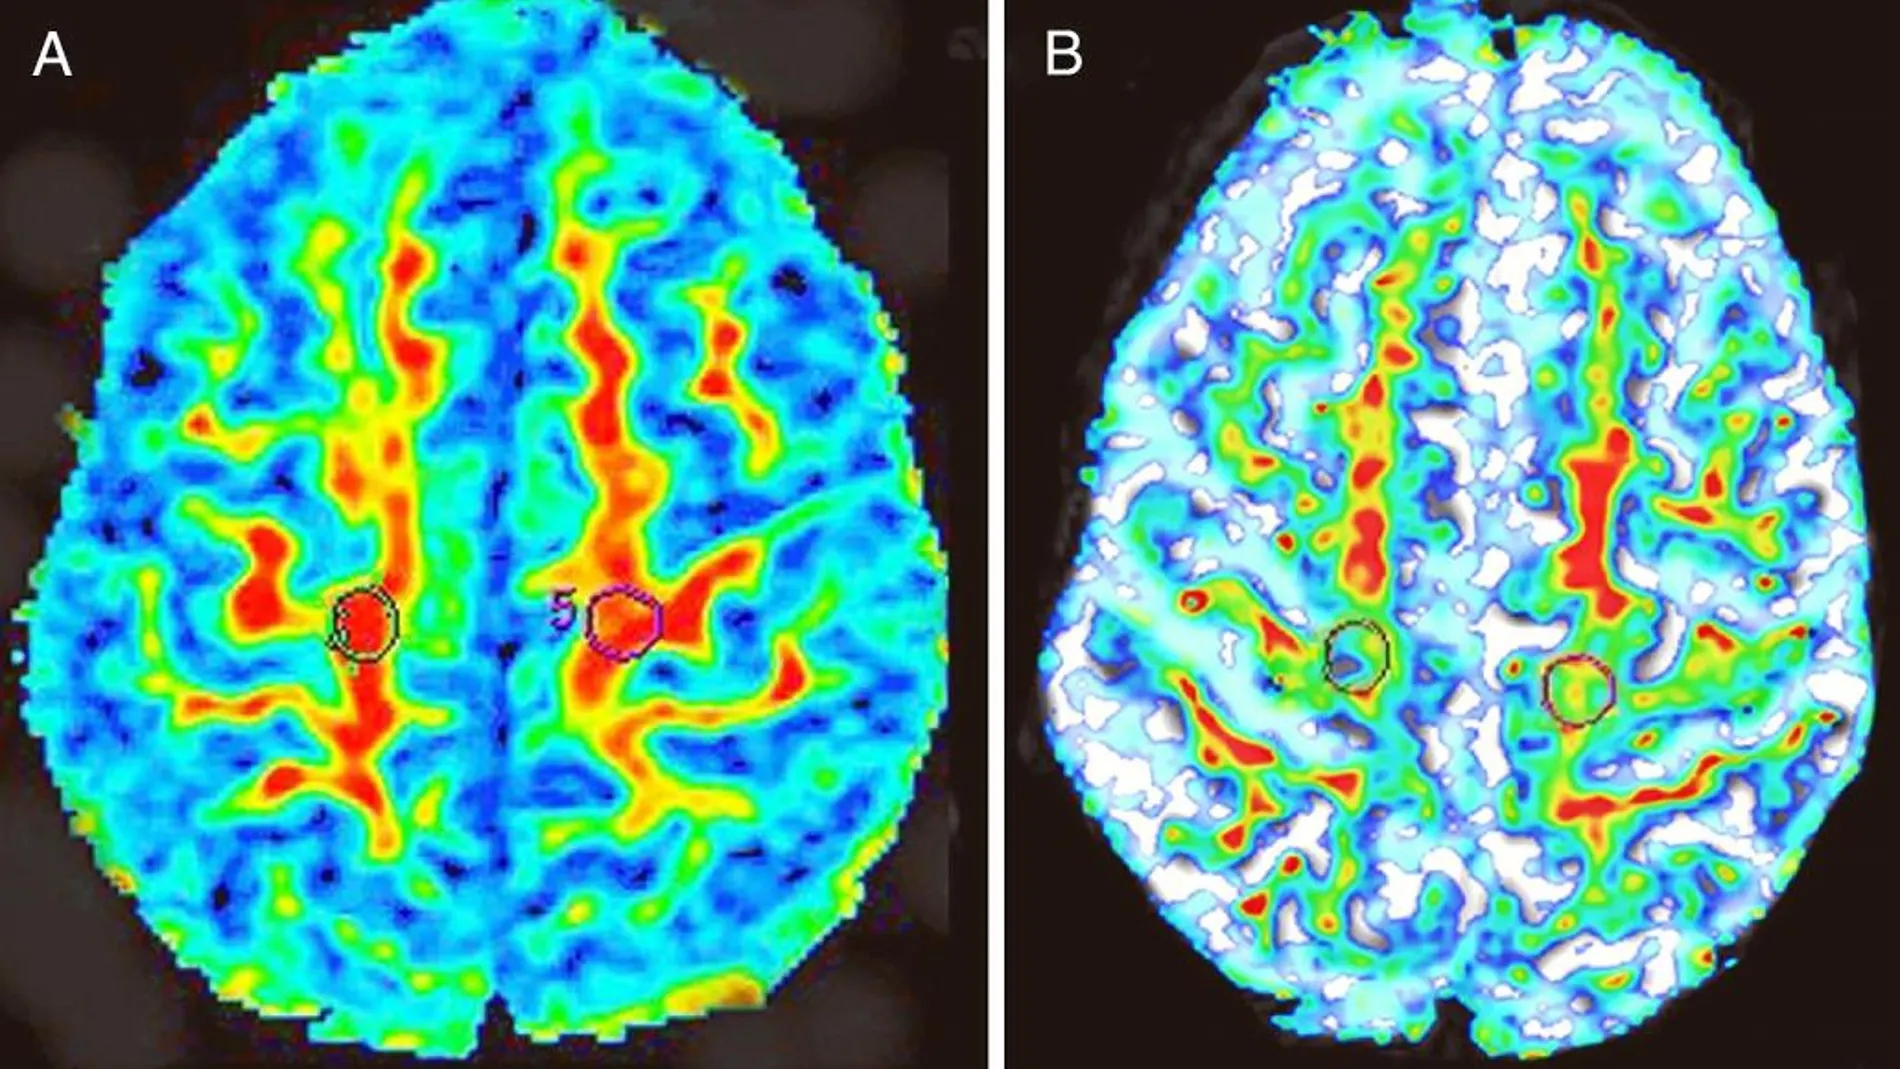

Un indicador eficaz de la enfermedad es la agregación de excesivas cantidades de proteína TDP-43 en el cerebro. De manera que se cree que eliminar esta proteína podría ser una buena estrategia terapéutica. Pero la TDP-43 es fundamental para que vivan las células. Acabar con ella no es buena idea.

¿Cuál es la relación entre estas dos sustancias y la enfermedad? Los investigadores de Stanford han diseñado ratones cuyas neuronas producen TDP-43 humana en grandes cantidades. Todos generan algunos síntomas similares a la ELA y empiezan a producir acúmulos de proteína en el cerebro. Paralelamente, a algunos de estos ratones se les modificó genéticamente para que no pudieran producir ataxina-2. Con sólo la mitad de ataxina-2 los ratones mejoraban ligeramente su esperanza de vida, pero cuando la ataxina era suprimida por completo los animales vivían hasta 20 veces más.